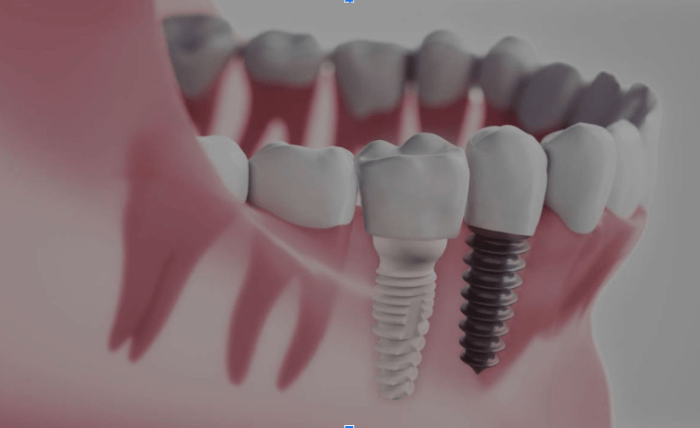

One of the most common causes of early problems with ceramic implants is improper placement during surgery. If the implant isn’t positioned correctly in the jawbone or the bone isn’t prepared properly, it can lead to issues such as implant failure or difficulty with osseointegration (the process where the implant fuses with the bone).

For an implant to properly fuse with the bone, there needs to be enough healthy bone in the area. If the bone is too soft or thin, the implant might not integrate well, causing it to become loose or fail. In such cases, additional bone grafting may be needed before the implant can be successfully placed.